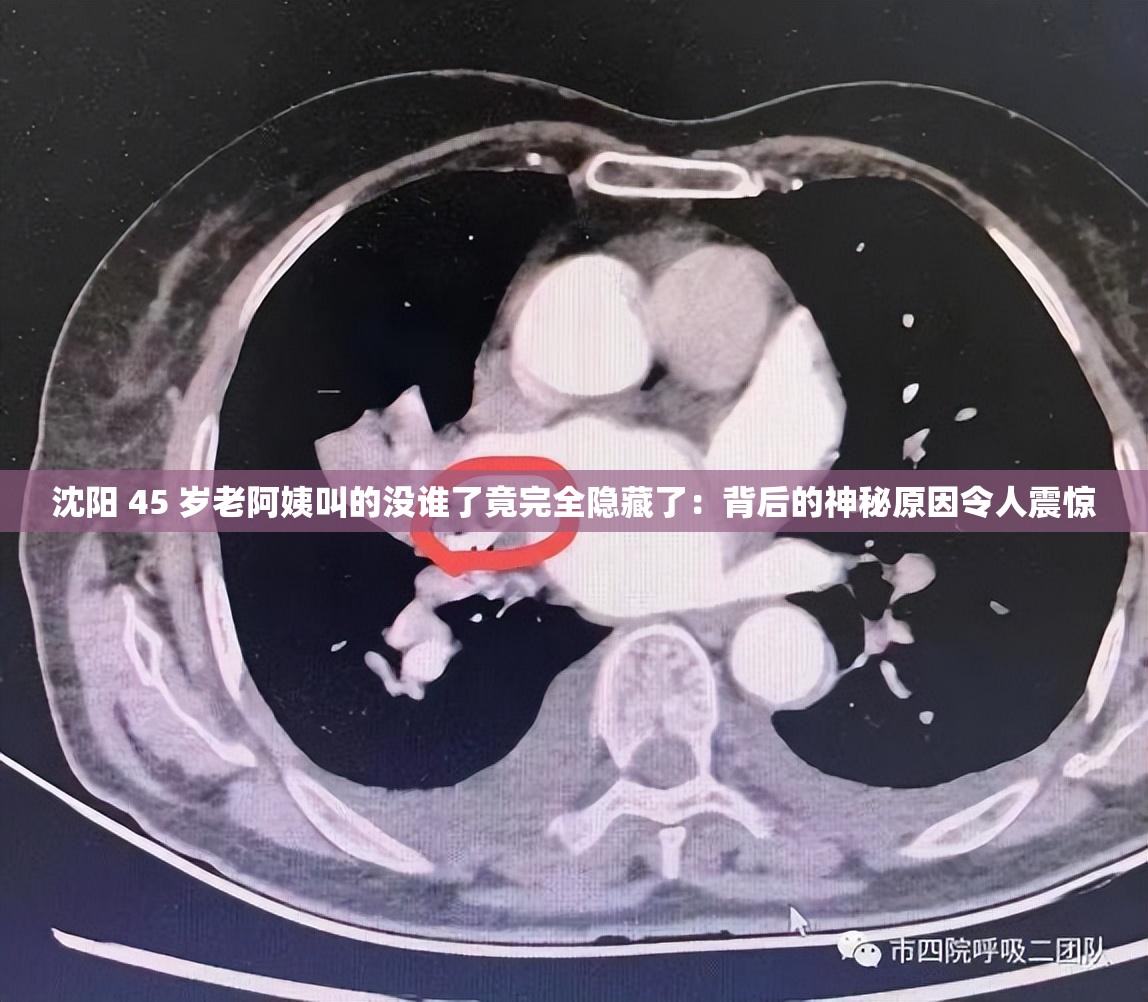

沈阳 45 岁老阿姨叫的没谁了竟完全隐藏了:背后的神秘原因令人震惊

沈阳 45 岁老阿姨的惊人秘密 在沈阳这座充满故事的城市里,一位 45 岁的老阿姨成为了人们茶余饭后谈论的焦点。她那独特的行为——叫得没谁了,却又完全隐藏起来,其背后的神秘原因令人震惊。 这位老阿姨原本过着平凡而普通的生活,在邻里间也未曾引起过多的关注。某一天开始,她的举止变得异常古怪。据周围的邻居回忆,...